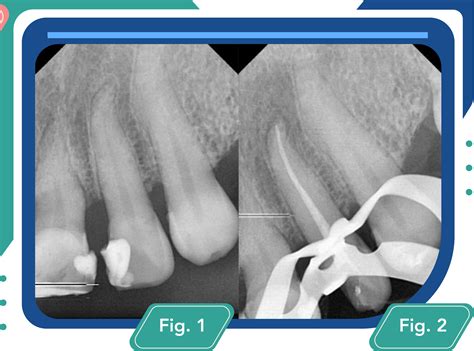

- Diagnóstico y Evaluación Inicial: Para ello, el endodoncista realiza una serie de pruebas radiográficas, valorando si la pulpa dentaria está infectada y determinando si la endodoncia es el tratamiento adecuado. Normalmente, antes de una endodoncia dental se debe hacer una revisión en profundidad del diente para conocer el daño total que se realizó a la anatomía bucodental. En algunos casos el problema no es reversible y no se puede salvar la pieza. El primer paso de una endodoncia es realizar una radiografía que ayudará a valorar la posible afectación de la pulpa o del nervio del diente.

- Preparación del Diente: El diente se prepara para la endodoncia con una fresa diamantada. De esta manera, se logra darle la amplitud necesaria para instrumentar los conductos. Si la pieza se encuentra muy perjudicada, es necesario cemento dental para reconstruir sus paredes. A continuación se empieza a preparar el diente con la ayuda de una fresa diamantada, intentando darle la amplitud suficiente para poder instrumentar los conductos. Acto seguido, una vez que se ha realizado el saneado de la caries de la pieza a tratar, se realiza un aislamiento con un dique de goma y su respectivo clamp, dejando aislada únicamente la pieza a tratar.